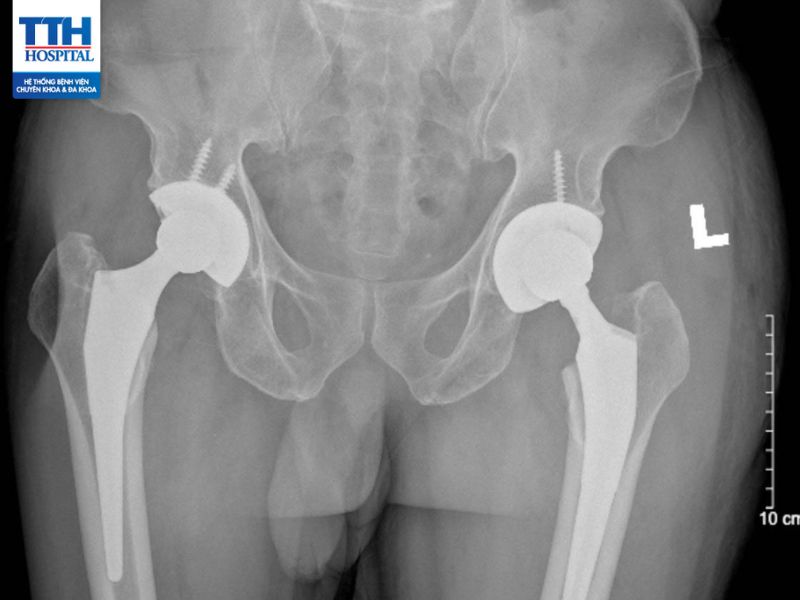

Thay khớp háng nhân tạo (artificial hip replacement) là một phẫu thuật chỉnh hình (orthopedic) thường được thực hiện để điều trị các vấn đề về khớp háng bị tổn thương hoặc thoái hóa nghiêm trọng.

Thoái hóa khớp háng là tình trạng bệnh lý thường gặp khi khớp háng mất dần tính linh hoạt và trở nên tổn thương do quá trình thoái hóa.